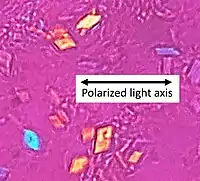

| Polarized light microscopy of CPPD, showing rhombus-shaped calcium pyrophosphate crystals with positive birefringence. | |

Arthrocentesis, or removing synovial fluid from the affected joint, is performed to test the synovial fluid for the calcium pyrophosphate crystals that are present in CPPD. When stained with H&E stain, calcium pyrophosphate crystals appears deeply blue ("basophilic").[10][11] However, CPP crystals are much better known for their rhomboid shape and weak positive birefringence on polarized light microscopy, and this method remains the most reliable method of identifying the crystals under the microscope.[12] However, even this method has poor sensitivity, specificity, and inter-operator agreement.[12]